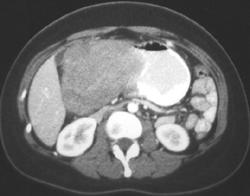

Bezoar Simulates A Tumor